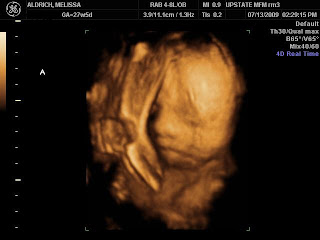

- Baby A is my shy stubborn one.

It was a good visit AND we got 3D ultrasound photos! I love how they are fascinated with their feet though it proved difficult to get face shots with all those feet. By the way, Baby B’s feet are the ones blocking Baby A’s shot. She did not want her sister to have the limelight!